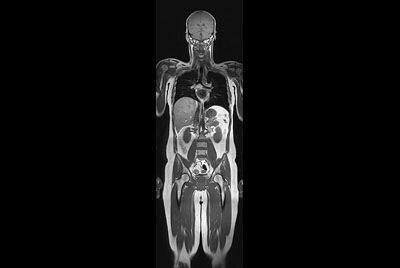

Total Torso with SmartShim

Whole Body imaging under 30 minutes on BlueSeal magnet

Total Torso overview

Total torso and liver

Total Torso imaging - High dS SENSE acceleration

Total Torso imaging - MultiVane XD

Whole Body imaging

Total Torso imaging

Total Body Imaging